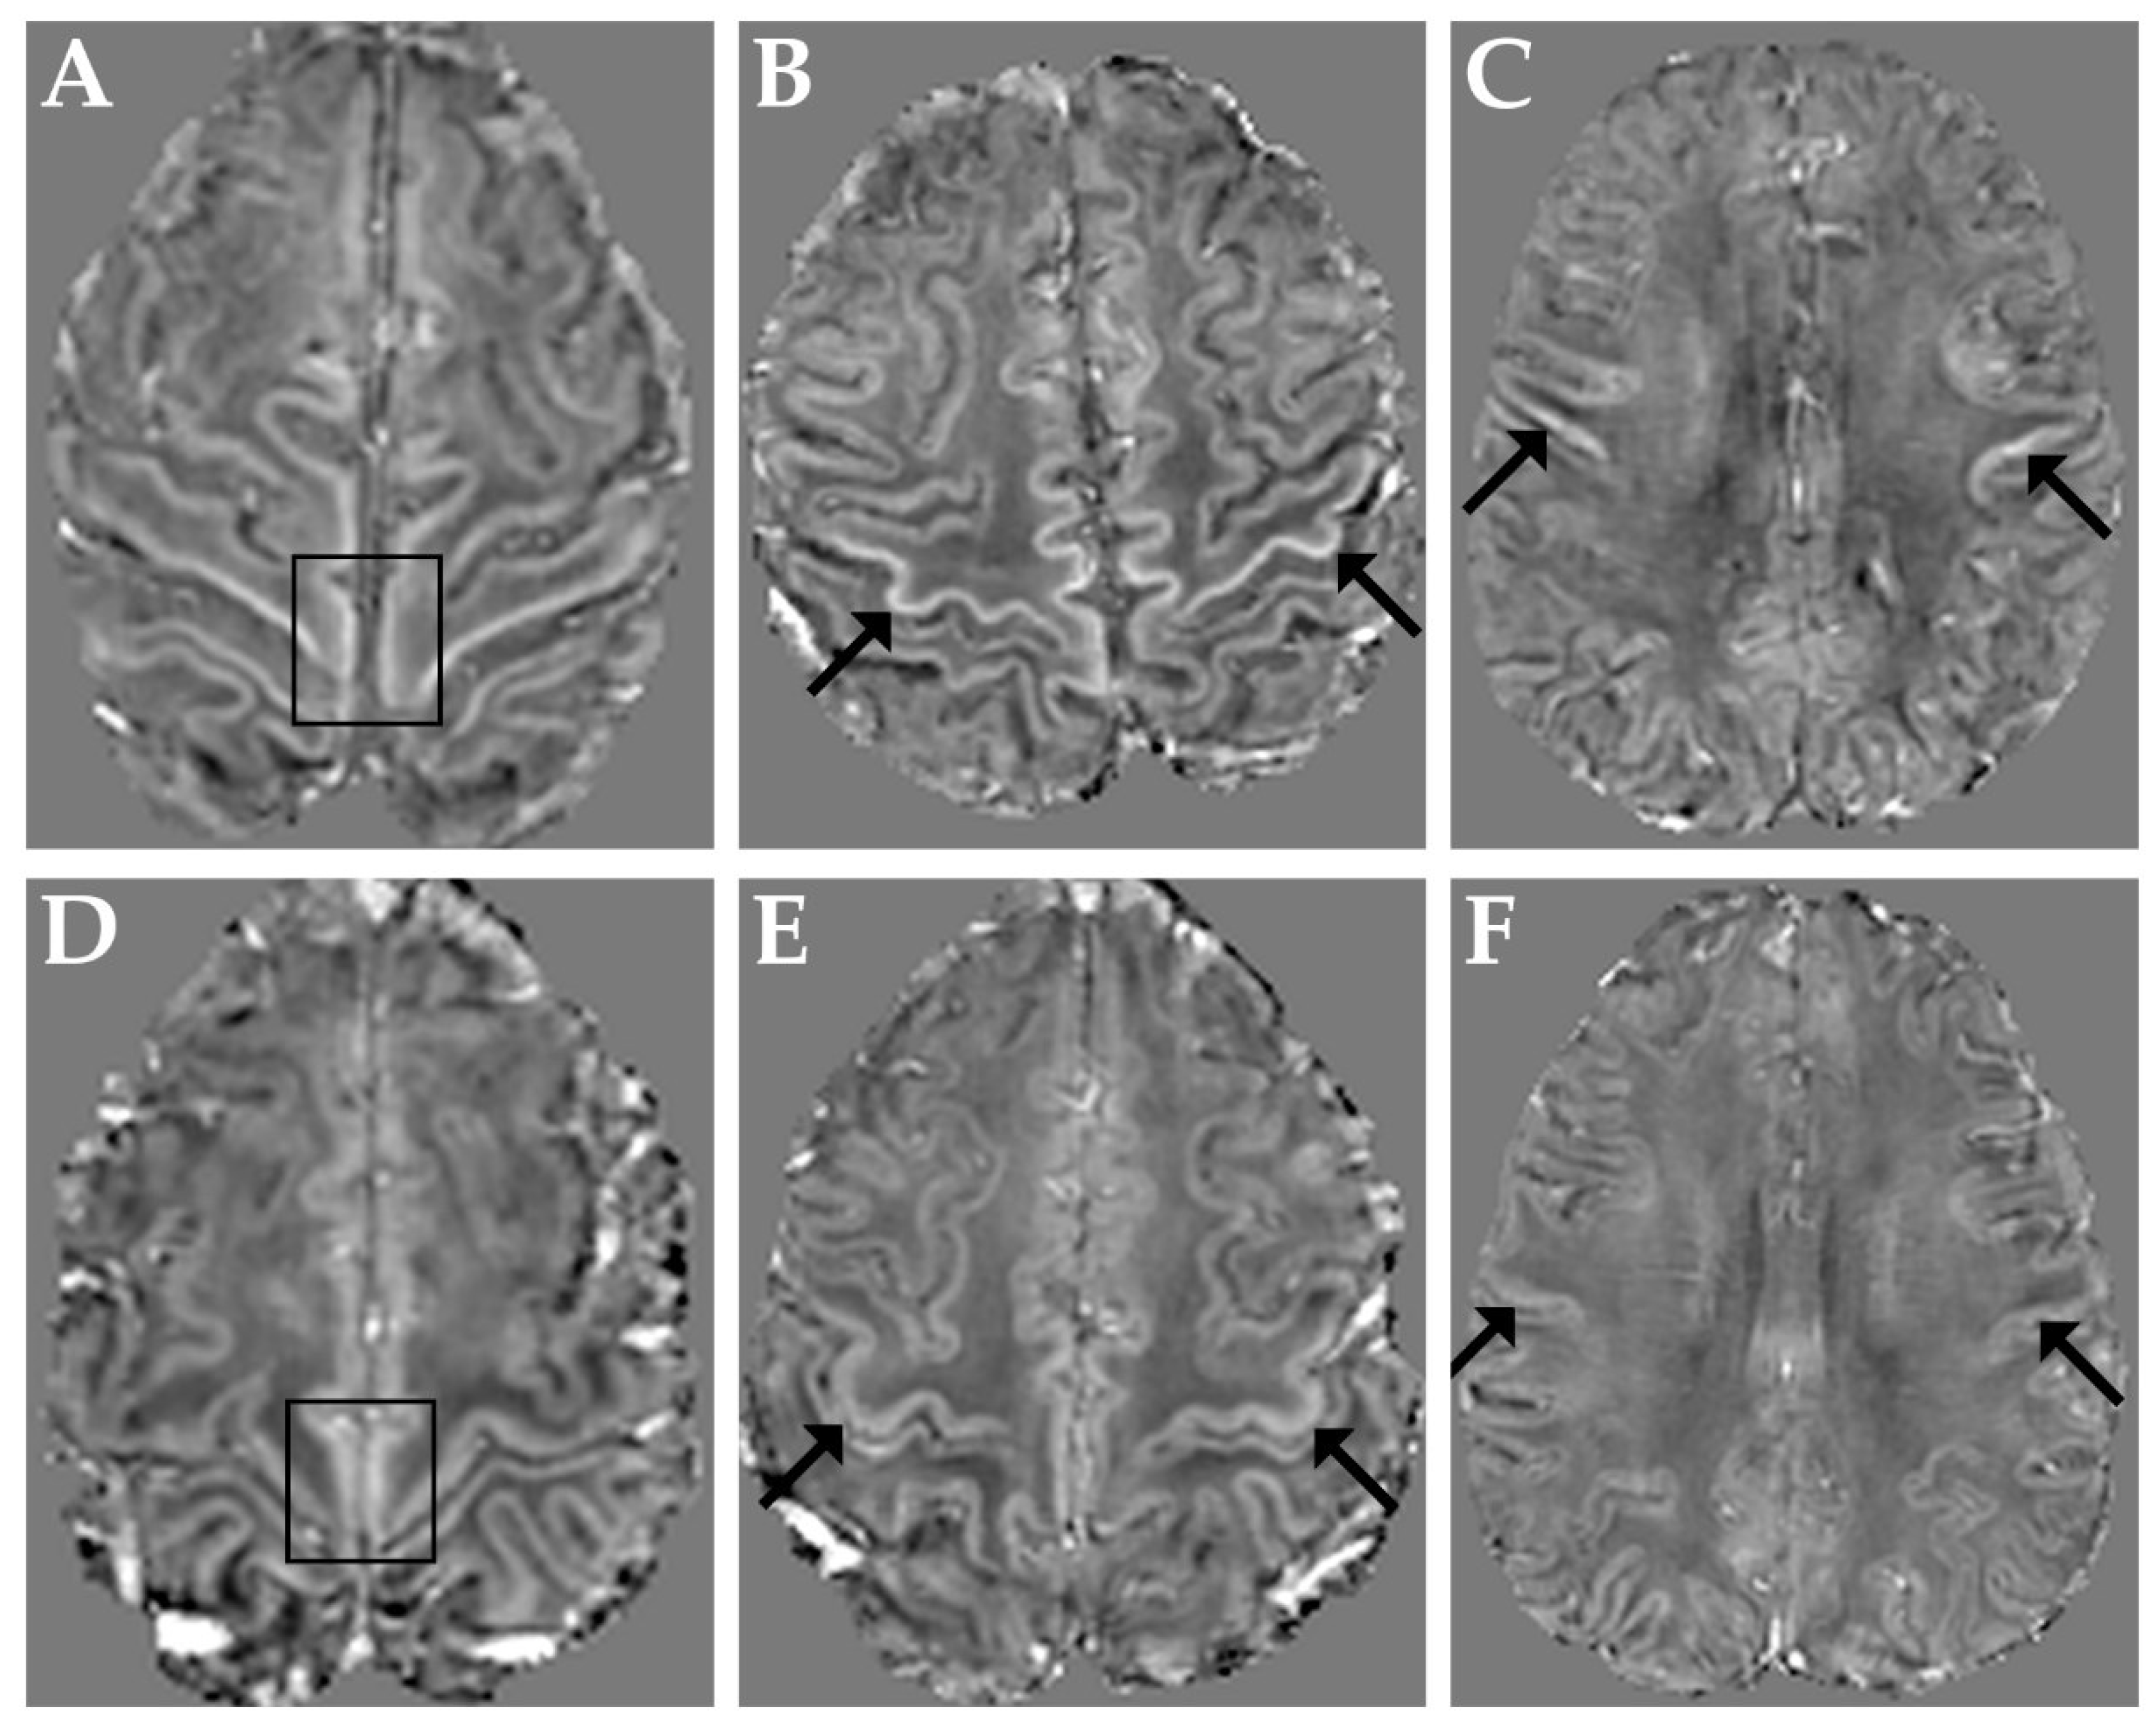

Figure 1 shows representative QSM images obtained in three ALS patients with M1 χ increase in the paracentral lobule, in the hand-knob and in the orofacial region (panels A–C, respectively) and, for reference, in a control subject (panels D–F).

Figure 1.

Top row: representative QSM images obtained in three ALS patients with M1 χ increase in the paracentral lobules (A), in both hand-knob areas (B) and in the orofacial regions (C). Bottom row: QSM images in a representative control subject at the level of the paracentral lobules (D), hand-knob (E) and orofacial regions (F). Arrows and boxes indicate corresponding regions in patients and control subject.